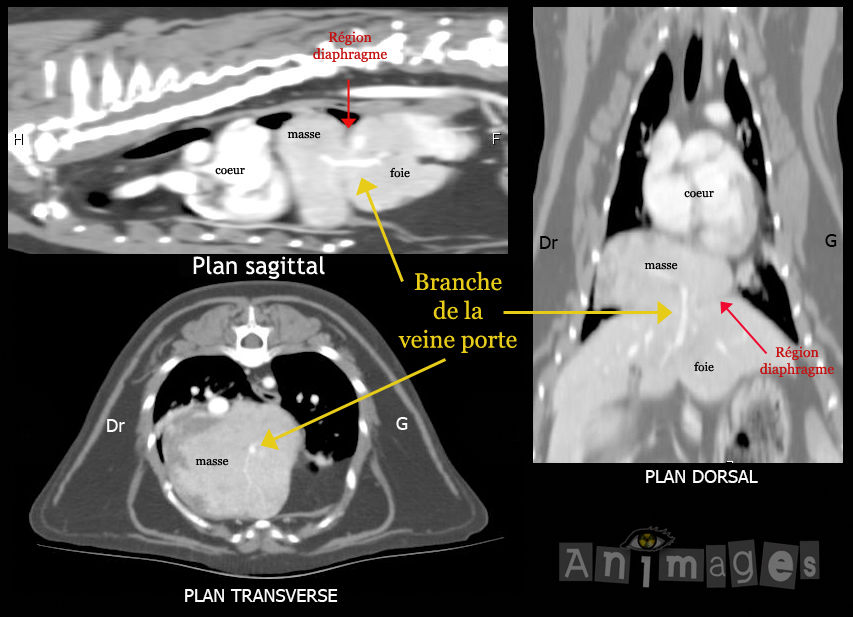

Tomodensitométrie